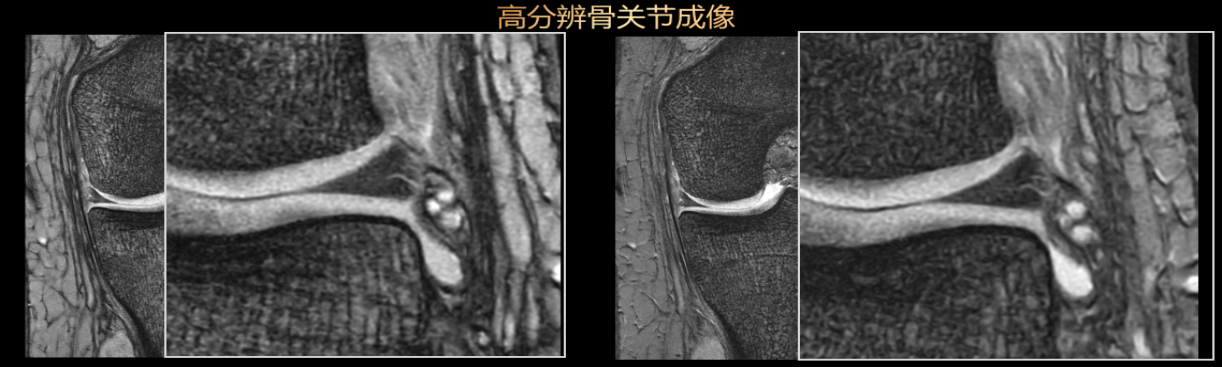

5.全身四肢关节高分辨成像,全脊柱成像,脊髓成像,三叉神经,臂丛神经,腰骶丛神经成像;同时还具备类CT扫描功能,可以清晰显示外伤、细微骨折等。